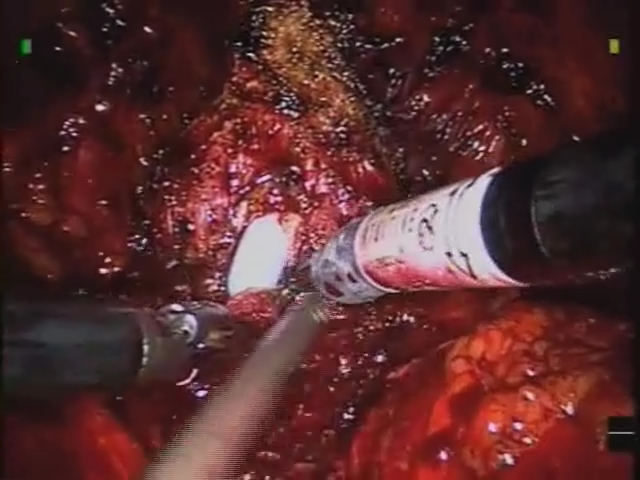

Robotic Repair of Rectovesic..

Robotic Repair of Rectovesic..

Rene Sotelo, MD; Robert J. De Andrade, MD; Oswaldo Carmona, MD; Juan C. Astigueta, MD; Alejandro Vel / CINE-MED